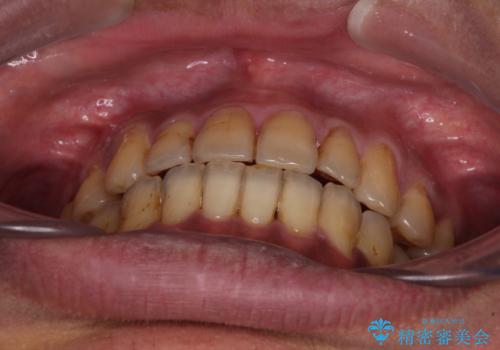

前歯のクロスバイトを改善 ワイヤー装置での非抜歯矯正

- 骨格的な咬み合わせのズレ、前歯のデコボコとクロスバイトを気にして来院された患者様です。

骨格のズレが顕著であると診断され、マウスピース矯正では奥歯の咬み合わせが整えにくいと判断し、ワイヤー装置による矯正治療を行うこととしました。

上下の叢生は速やかに改善できましたが、右側のクロスバイトの改善に1年以上の期間を要しました。